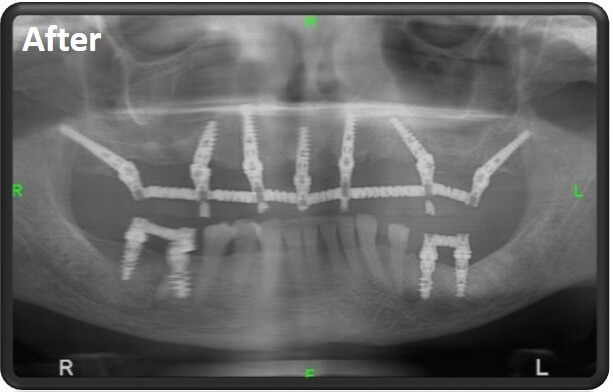

The implants are required to be strong and stable, since they carry a bridge on which are connected the dental crowns, that are in fact, the new teeth.

This is why several different implants have been developed that allow to perform a connection to the jawbone in angles that could even reach up to 45 degrees and their purpose is to create the best anchor possible in the correct location and angles where the jaw is thickest, strongest and most stable.

These implants are designed to be used in full jaw dental implant, for either the upper jaw or lower jaw. These implants are utilized in cases when the jawbone condition is relatively good and there is ample jawbone in order to connect the implants directly as screws.

The screw position of these implants is mostly by vertical screwing and they are very similar to the natural teeth’s way of anchoring.

Their lower part of the screw connects to the cortical bone (jawbone) and a top part that can connect through a wide range of angles to a bridge holding the crowns.

The cortical implants can be implanted at uneven angles up to 45 degrees.